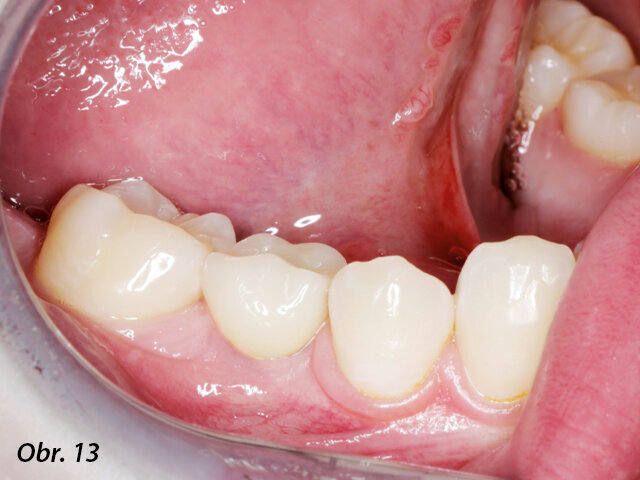

Definitivní náhrada v ústech pacientky.